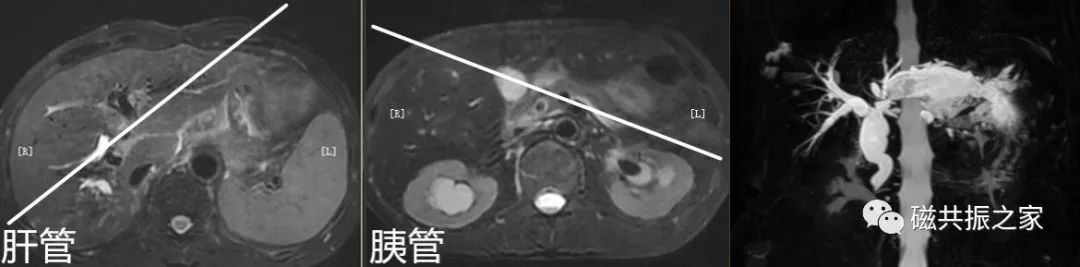

主要在横轴位上定位,采用厚层模块扫描,采用放射状的定位方式;并在冠状和矢状位上调整FOV的上下位置。

呼吸触发或屏气的薄层冠状面3D MRCP序列

在横轴位和矢状位上定位,定位与主胰管走形一致,如需了解肝内胆管情况可与肝内胆管走形定位扫描。扫描范围包括肝管、胆管、胆囊、胰管,合理调整扫描范围,需包括整个病变范围。

3D MRCP模块扫描范围尽量不要包括前腹部,同时添加相应的饱和带,可以有效的改善前腹部呼吸运动带来的伪影。同时扫描模块能避开主动脉的尽可能避开主动脉区域。